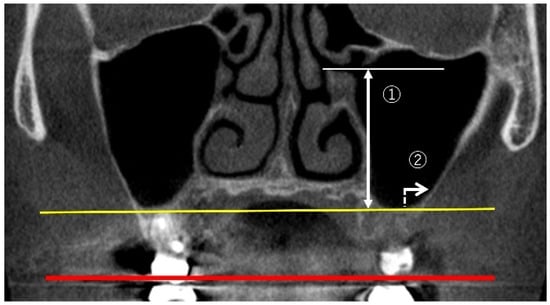

2.3.3. Measurement of Sinus Membrane Thickness (SMT)

2.3.5. Maxillary Sinus Septa